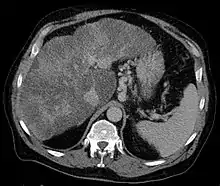

| Isolated gastric varices of Sarin classification IGV-1 seen on gastroscopy in a patient with portal hypertension | |